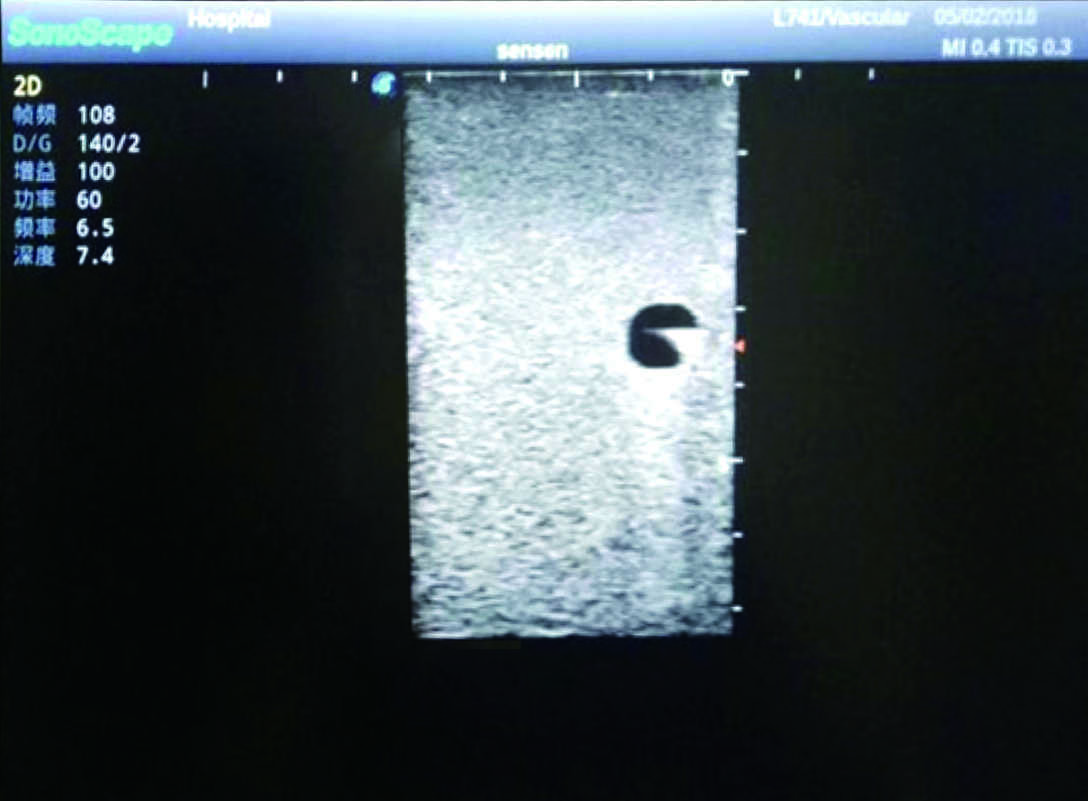

2) It can be used by real ultrasound machines

3) Clear and real images of the tissues and organs (basilic vein and superior vena cava)

5) Observe the guide wire marches